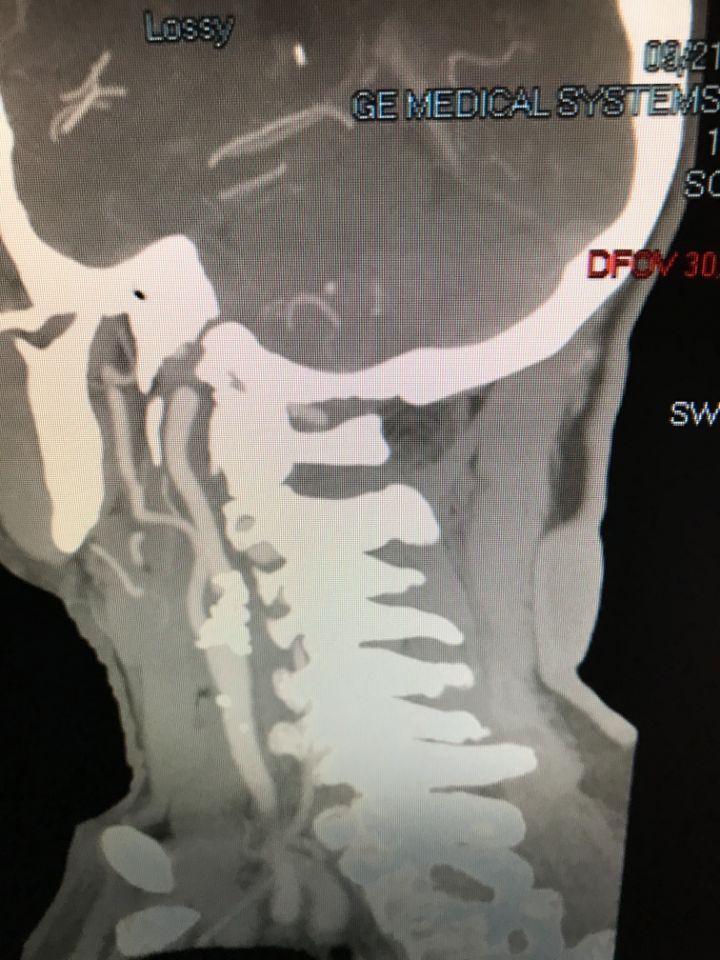

Ecco alcune immagini degli interventi eseguiti dal Dottor Viglione presso il suo studio a Cuneo.